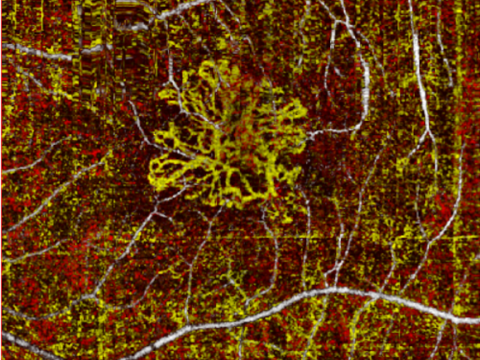

Δευτερογενής καταρράκτης

Σε ένα ποσοστό των ασθενών που έχουν υποβληθεί σε εγχείρηση αφαίρεσης καταρράκτη δημιουργείται ο δευτερογενής καταρράκτης ή ψευδοκαταρράκτης και μπορεί να συμβεί εβδομάδες, μήνες ή χρόνια μετά την επέμβαση. Αυτό οφείλεται στην οπίσθια μεμβράνη του φακού (οπίσθιο περιφάκιο) που έχει θολώσει με αποτέλεσμα η όραση σταδιακά να μειώνεται και να εμφανίζει παρόμοια συμπτώματα με αυτά πριν την επέμβαση καταρράκτη. Ο γιατρός σας μπορεί να το αποκαλέσει «θόλωση οπισθίου περιφακίου» και θεραπεύεται με μια απλή εφαρμογή λέιζερ στο ιατρείο (YAG Laser capsulotomy/ σχάση οπισθίου περιφακίου με YAG Laser). Το λέιζερ δημιουργεί ένα άνοιγμα στη θολή κάψα και η όραση αποκαθίσταται.